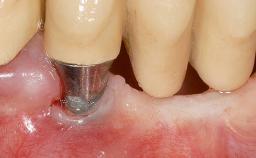

Early Implant Placement, Contour Augmentation, and Autologous Connective-Tissue Graft Using a Tunneling Technique to Replace an Upper Incisor with Generalized Gingival Recession

| # of Implants | 1 |

| Type of Implants | Reduced-Diameter|Two-Piece |

| Soft Tissue Grafting | Simultaneous |